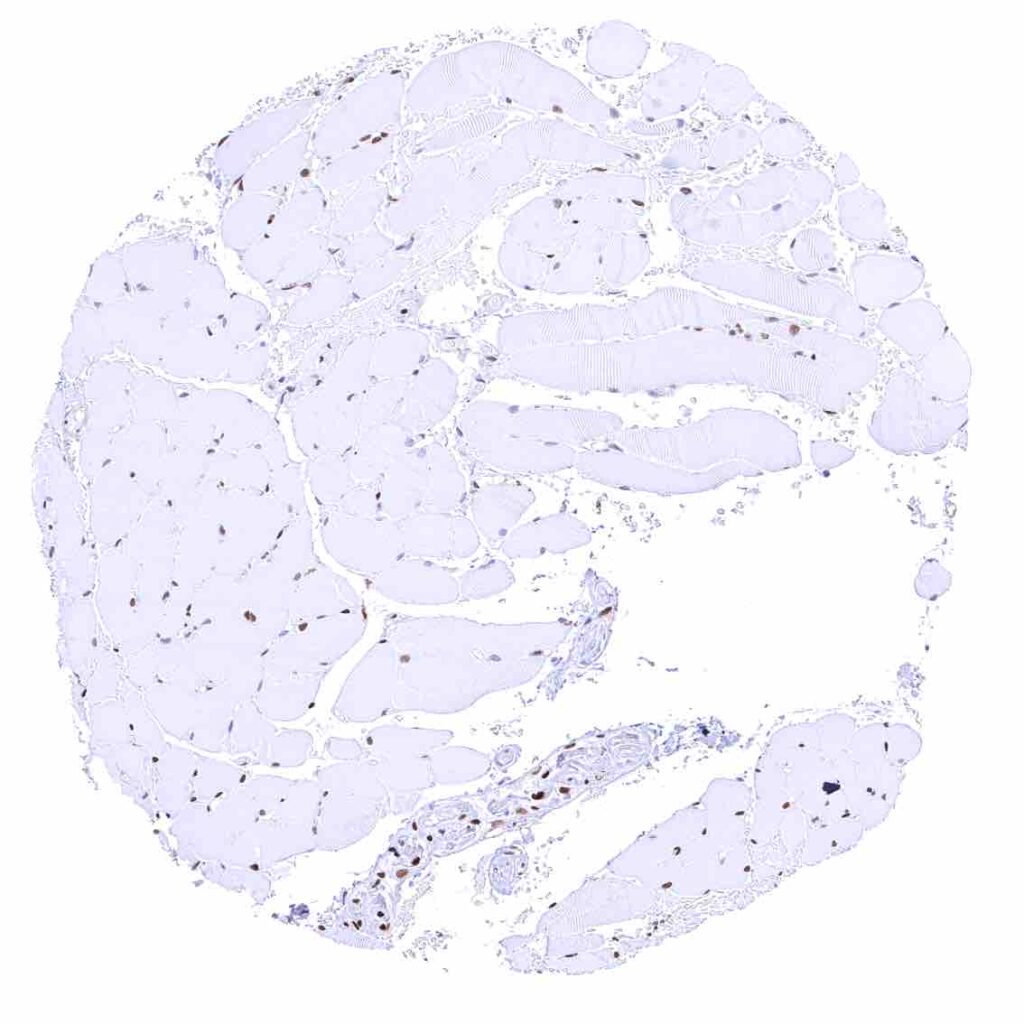

Heart muscle – Distinct nuclear p27 staining of stroma cells while myocytes are largely negative.